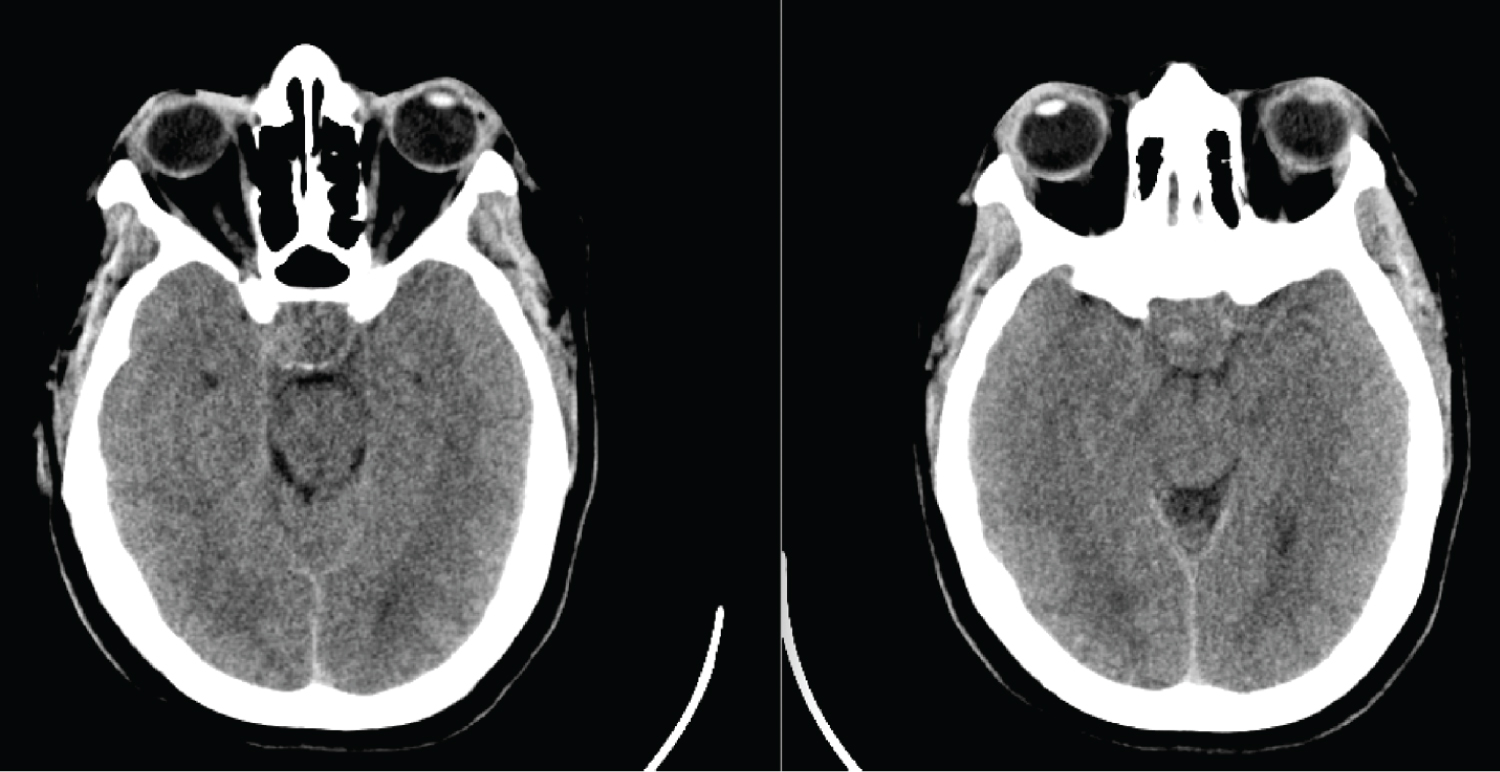

CT scan of the brain showed a hypodense region in the territory of the right ACA and MCA, consistent with an acute ischemic infarct (Figure 1), but no significant mass effect or midline shift. A hyperdense mass was noted in the region of the pituitary fossa, suspicious for a hemorrhage in a pituitary adenoma. The patient had an urgent MRI/MRA of the brain, which revealedanapoplectic grade 3 pituitary adenoma. There was compression of the cavernous segment of the right ICA (Figure 2), which was the likely culprit for her ischaemic infarct.

Figure 1: Non-contrast CT scan of the brain on presentation, showing a heterogenous mass in the sella with later extension in the right cavernous sinus. View Figure 1